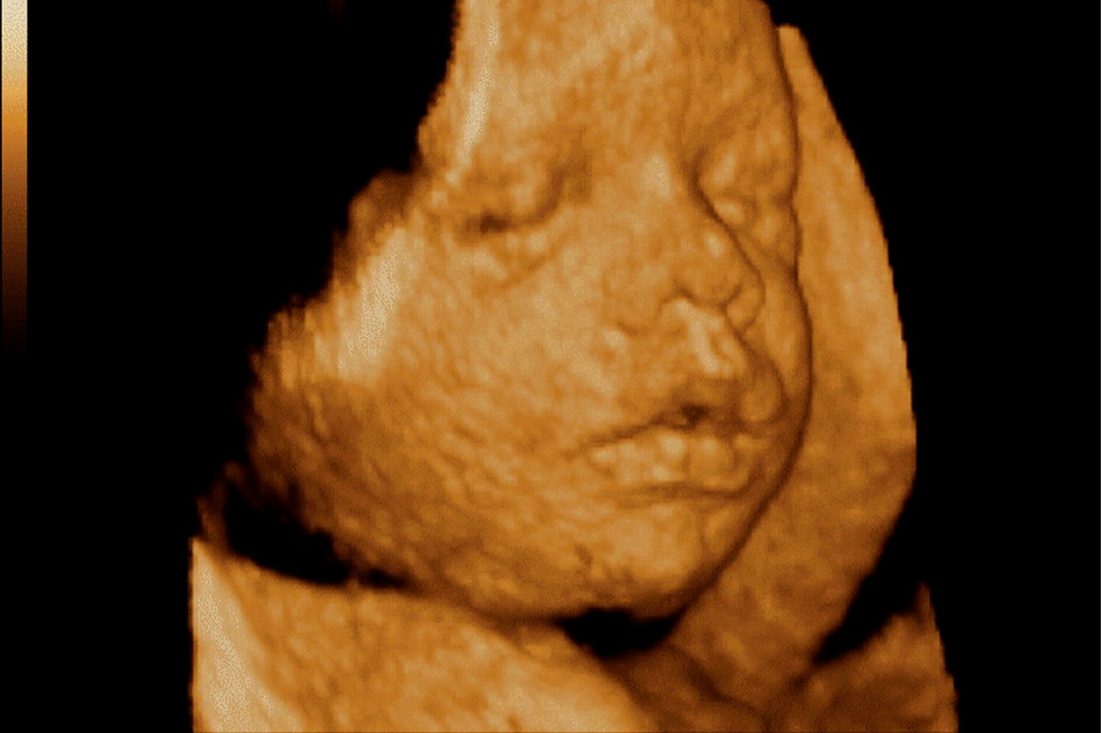

Snímek z 3D ultrazvuku

Při 3D ultrazvuku je série klasických dvourozměrných (2D) obrázků rekonstruována do obrázku 3D a vy tak máte možnost vidět téměř reálný plastický obraz svého dítěte.

4D zobrazení vzniká tím, když se ke 3D zobrazení přidá další dimenze – čas. Výsledkem rychlého snímáním 3D obrázků je tak video v reálném čase čili 3D snímky nejsou statické, ale dají se do pohybu a vy vidíte reálný pohyb miminka.